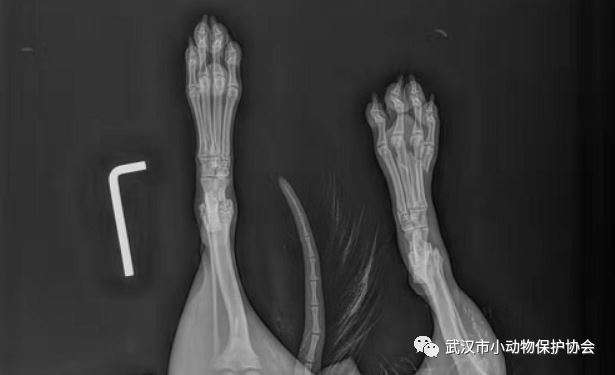

救助经过:发现人联系协会说发现一只小猫脚受伤,被他关在中国银行大厅内希望我们前往救助,经救助后带至宠物康发现小猫双后脚疑似被电梯夹伤,部分脚趾已经缺失,已做处理。